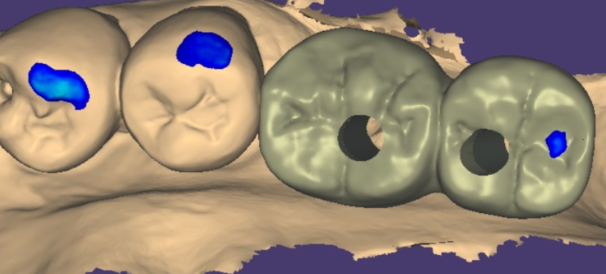

상일동역 치과에서는 디지털 장비를 사용해

이 모든 과정을 진행합니다.

때문에 구강 내를 그대로 재현해 주고

오차 없이 보철물 제작이 가능합니다.

231221

모든 과정이 디지털이기에

보철물이 들어갈 모습을 예측 할수도 있답니다.